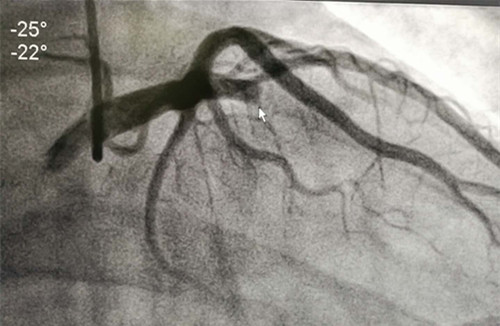

冠脈造影結(jié)果如下圖:

醫(yī)患互信,方一切可能,患者手術(shù)過程進(jìn)展的非常順利,心臟支架的成功置入開通了血管,患者胸痛立即緩解,挽救了瀕死的心肌,有效地改善患者的心功能,提高了生活質(zhì)量。心血管內(nèi)科此次開展的急診冠脈介入診療術(shù)是臨滄市首例急診PCI,手術(shù)的成功實施,填補(bǔ)了臨滄市此類技術(shù)的空白,標(biāo)志著臨滄市人民醫(yī)院心血管內(nèi)科踏上了一個新的臺階。目前,該名患者在醫(yī)護(hù)人員的精心治療與護(hù)理下已好轉(zhuǎn)出院。

支架置入術(shù)后造影結(jié)果如下圖: